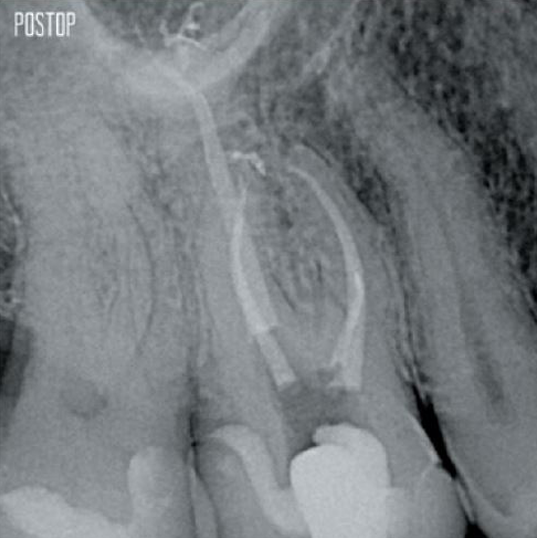

Photos courtesy of Dr. Ahmed Salman

More dentin preserved. Appropiate shaping, irrigation, and obturation ensured.

Successful root canal treatment starts with adequate access to the pulp chamber. The ideal procedure provides access to root canal orifices with minimal loss of dentin.

A Conservative Endodontic Cavity (CEC) is recommended with the TruNatomy® system.

The union of the file geometry, regressive tapers and the slim, highly-flexible wire enables efficient root canal treatment while removing only dentin where clinically needed.1